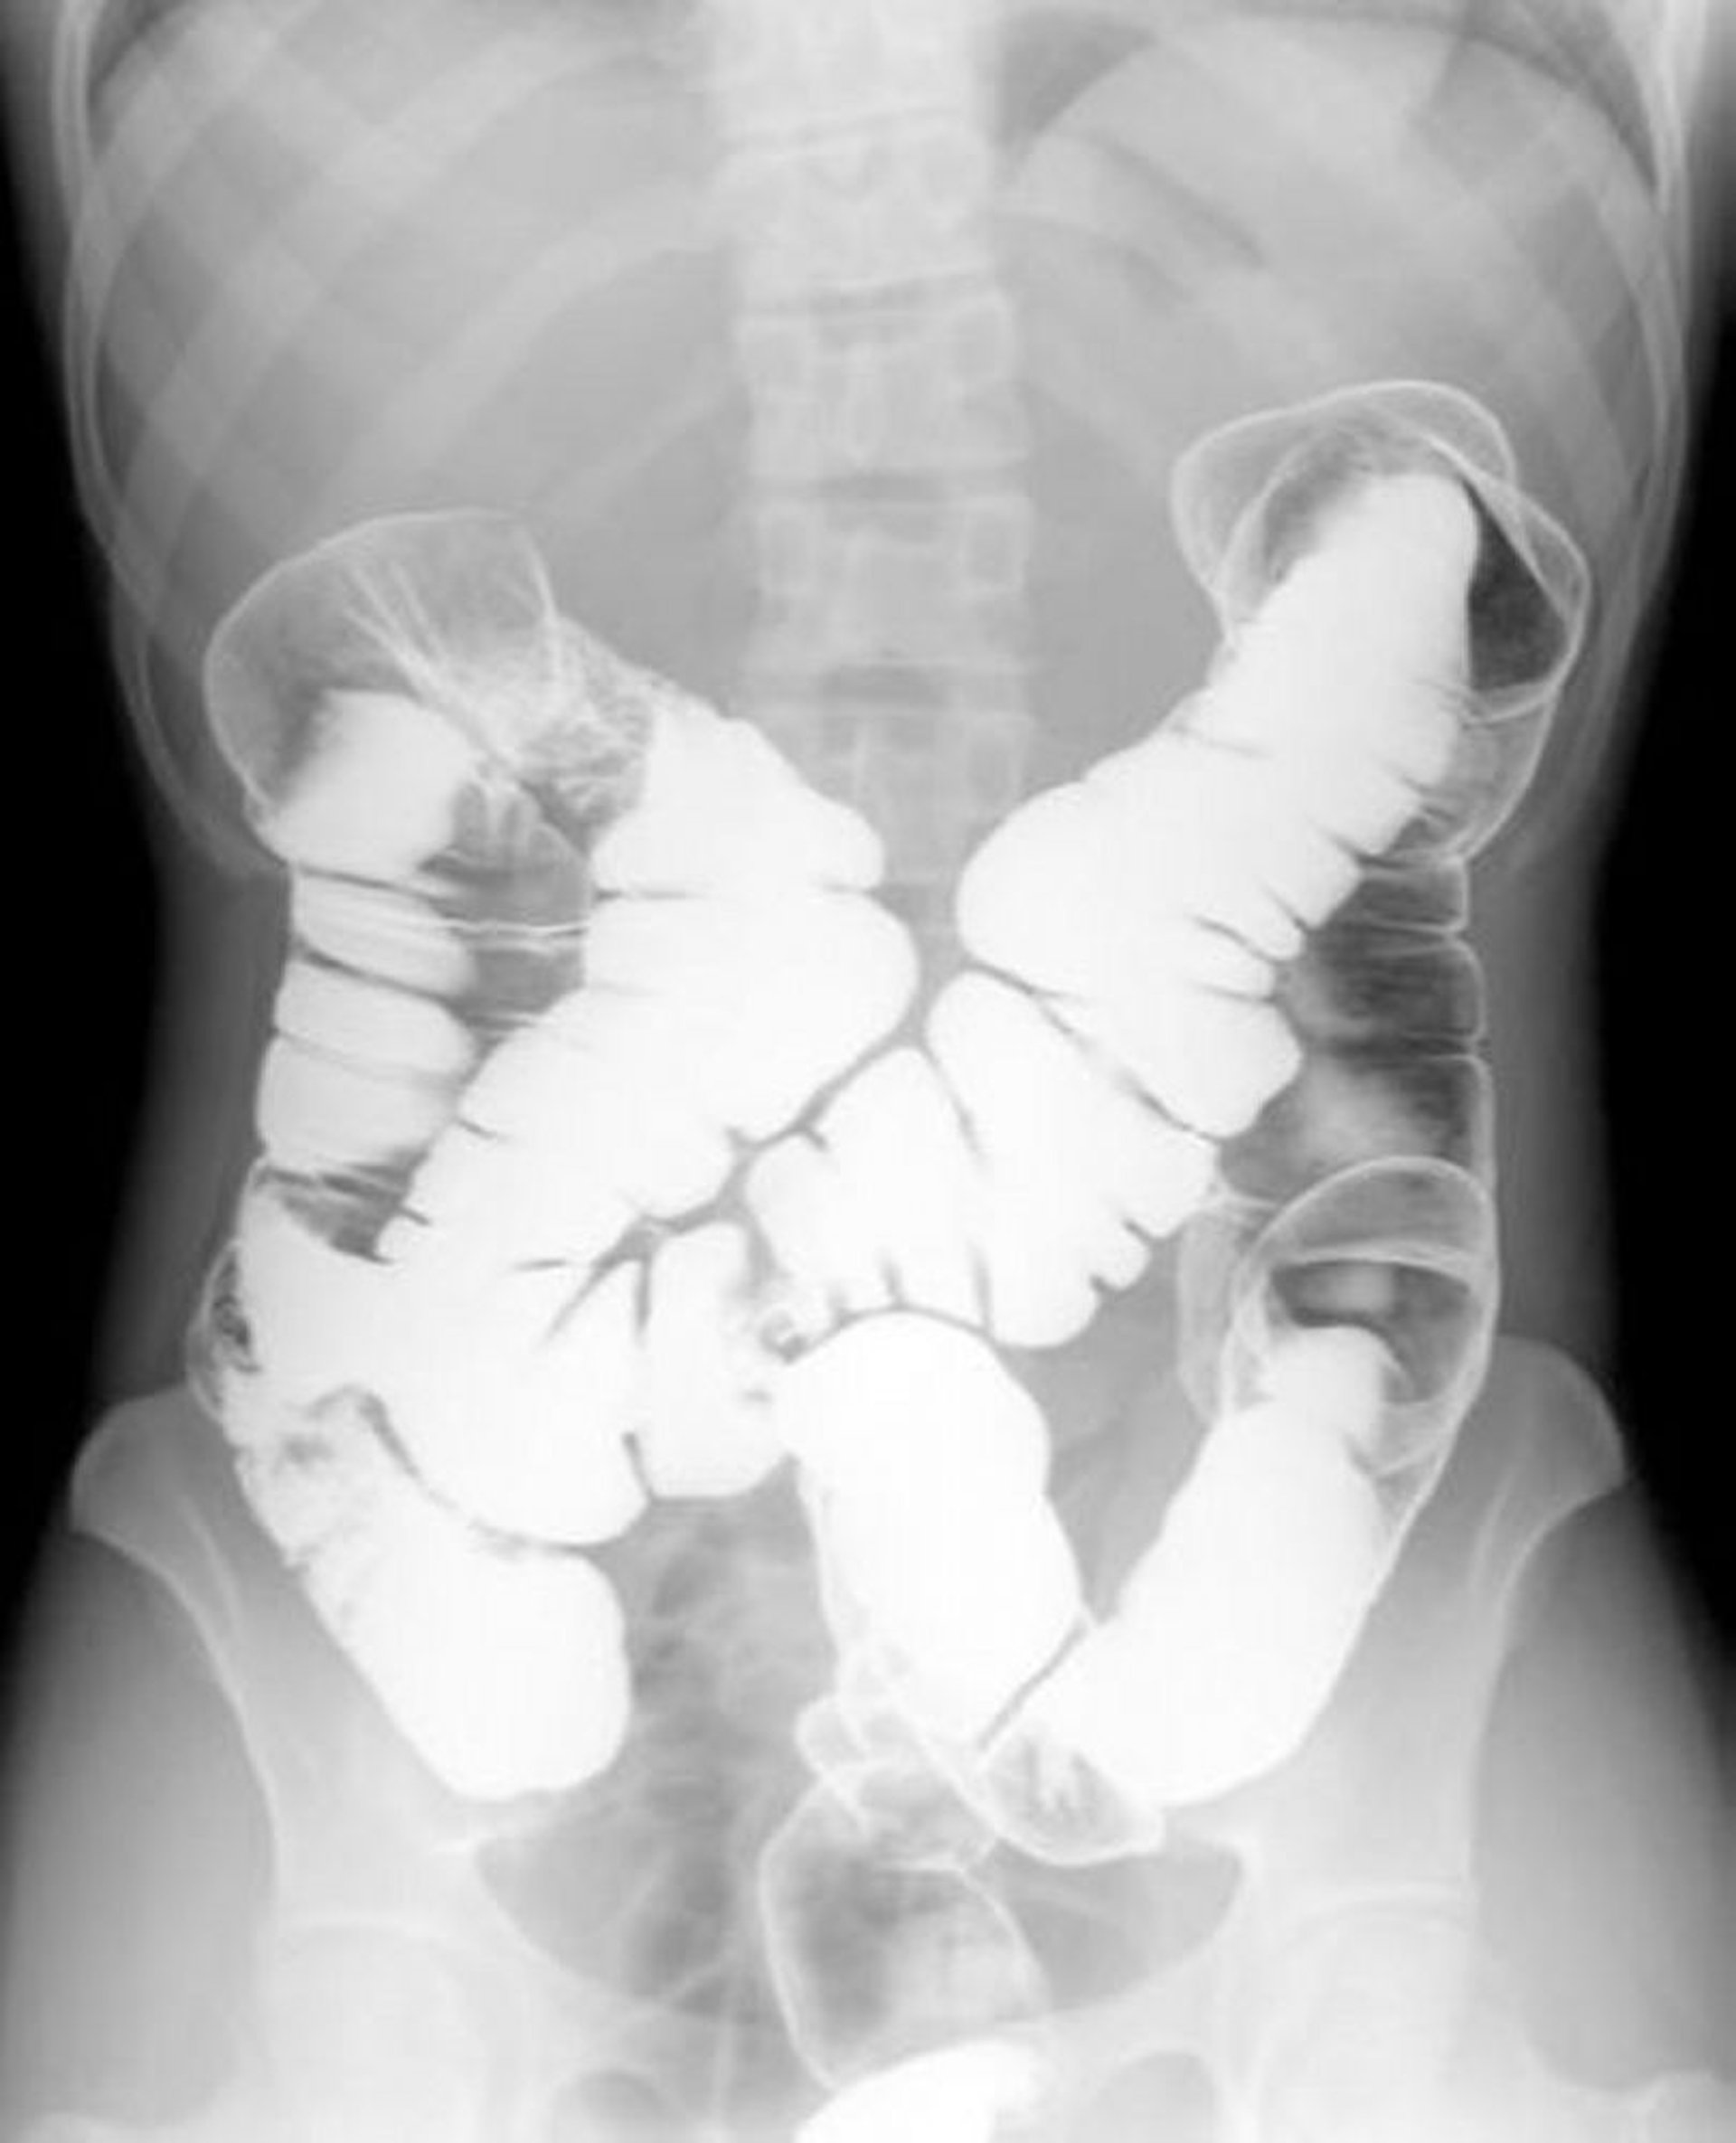

Lavement baryté en double contraste montrant une anatomie normale

Cette image montre la répartition de l'air et du baryum dans un côlon normal.